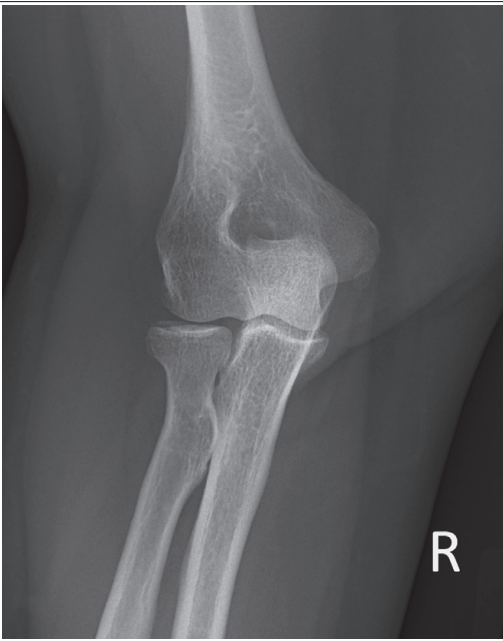

More than 1/8 of the radial head is superimposing with the ulna

Internal rotation

Less than 1/8 of the radial head is superimposing with the ulna

External rotation

What is wrong with this external oblique elbow?